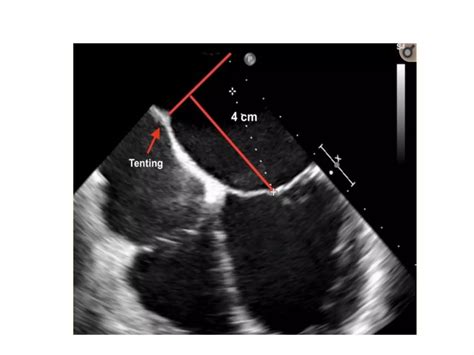

Preparation for a Mitral Valve Clip procedure involves several diagnostic tests to map the heart's anatomy. These typically include an echocardiogram—specifically a transesophageal echocardiogram (TEE)—which provides detailed images of the valve. On the day of the procedure, you will be under general anesthesia.

• mitral valve clip echo